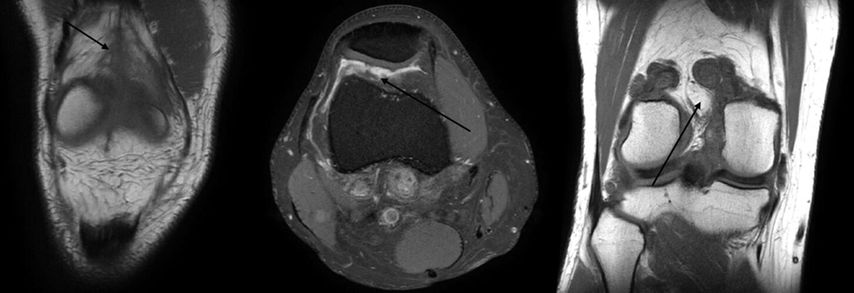

Um eine mögliche Destruktion des Knochens beurteilen zu können, ist die Durchführung eines konventionellen Röntgenbilds zu empfehlen. Die Magnetresonanztomografie (MRT) ist neben dem klinischen Erscheinungsbild der diagnostische Goldstandard. Neben der Ausdehnung zeigt die MRT auch bei methodenspezifischen Sequenzen Hämosiderinablagerungen, welche in der Literatur teilweise als pathognomonisch für das Vorliegen einer PVNS beschrieben werden (Abb. 2).

Abb. 2: MRT-Bilder eines 41-jährigen Patienten mit rezidivierenden Ergüssen, Schmerzen und Kniegelenksschwellungen. Es zeigt sich eine diffuse PVNS sowohl ventral als auch dorsal des Kniegelenks. Therapeutisch wurde der Patient einer radikalen offenen Synovektomie mit adjuvanter RSO unterzogen